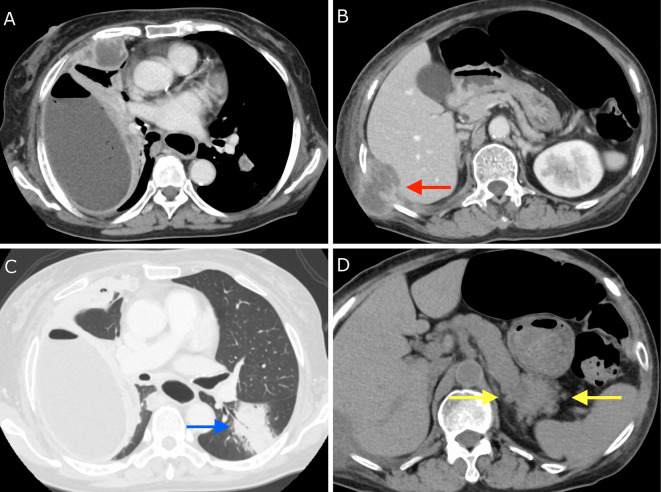

Empyema Necessitatis with Pancreatic Involvement Caused by Actinomycosis.

放线菌病所致必要脓胸伴胰腺受累。